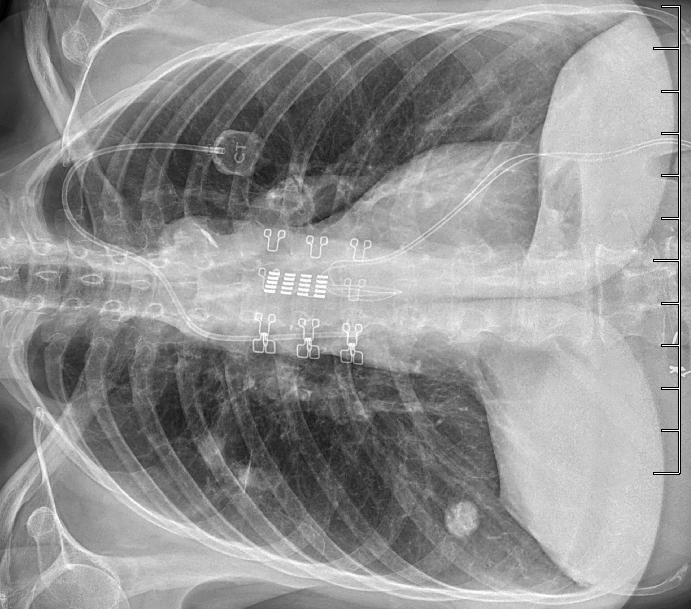

In this series, medical scans—MRI images, X-rays, and other diagnostic views—are transformed into intimate portraits that merge the clinical with the deeply personal. Each work intertwines medical imagery with biographical details, creating a layered visual narrative that honors both the physical realities of illness and the inner lives of those who endure them.

The exhibition features representations of conditions such as multiple sclerosis, lung cancer, hip and knee replacements, a broken wrist, miscarriage, and heartache—each one a story of endurance, adaptation, and faith. The artist wishes to express her gratitude to the patients and their families who entrusted her with creating artworks as unique and special as they are while acknowledging that recovery is never an individual journey; it extends to loved ones who must also heal, grieve, and rediscover vitality in the face of loss or uncertainty.

Mixed media pieces of art derived from the combination of medical scans, surveys from family and friends and genuine creativity from the creator, these artworks are one of a kind.